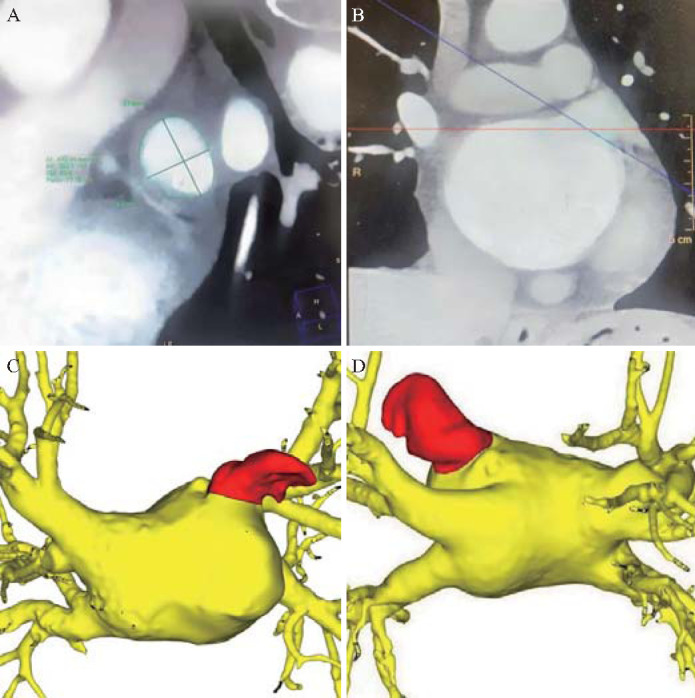

目的:分析瓣膜性心脏病合并心房颤动患者瓣膜手术中合并左心耳夹持术的有效性和安全性。方法:分析南昌大学附属第二医院2017年1月至2023年6月在心脏瓣膜手术中合并左心耳夹闭的患者58例,其中主动脉瓣置换术1例,二尖瓣置换术(或瓣膜成形术)+三尖瓣成形术49例,双瓣置换术+三尖瓣成形术8例(合并冠状动脉搭桥术3例)。术后随访3 ~ 36个月[(16.69±6.61)个月],观察患者心功能变化及严重不良并发症发生情况。结果:体外循环时间为75 ~ 145 min[(102.50±21.03)min],主动脉交叉夹持时间为35 ~ 80 min[(58.02±14.63)min]。术后ICU住院时间1 ~ 5天[(2.47±0.82)d],术后住院时间7 ~ 22天[(10.84±2.69)d]。心脏超声提示所有病例左心耳完全闭合。在随访期间,54例患者的纽约心脏协会(NYHA)功能分类得到改善。未见左心耳相关出血事件及其他围手术期并发症;随访期间无脑梗死、肢体栓塞事件或死亡病例发生。结论:对于瓣膜性心脏病患者,在心脏瓣膜手术中合并左心耳夹持具有明确的疗效和安全性,中期随访无严重不良事件发生。

Results: The cardiopulmonary bypass time ranged from 75 to 145 min [(102.50±21.03) min], and the aortic cross-clamp time ranged from 35 to 80 min [(58.02±14.63) min]. The length of postoperative intensive care unit stay was 1 to 5 days [(2.47±0.82) d], and the length of postoperative hospital stay was 7 to 22 days [(10.84±2.69) d]. Cardiac ultrasound indicated complete closure of the left atrial appendage in all cases. During the follow-up, New York Heart Association (NYHA) functional classifications were improved in 54 patients. No left atrial appendage-related bleeding events or other perioperative complications were observed; and no cerebral infarction, limb embolism events, or mortality cases occurred during the follow-up.